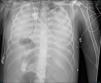

A 19-year-old woman, with a past medical history of Steinert's myotonic dystrophy, intubated due to severe respiratory distress after an exploratory laparotomy for intestinal pseudo-obstruction. In tracheal aspirate, Escherichia coli without resistance mechanisms. Very poor pulmonary mechanics (compliance < 2 mL/cmH2O) and no response to prone positioning, veno-venous ECMO is cannulated, and given the high airway pressures with 4 mL/kg of ideal body weight, ventilation is switched to airway pressure release ventilation (APRV): high pressure 15 cmH2O; high time 6 s; low time 0.3 s. Initially 10 mL of exhaled volume. Radiographic progression is shown in the images (Fig. 1: day 0; Fig. 2: day 2; Fig. 3: day 5). This case is an example of how APRV ventilation while ensuring gas exchange with ECMO can be useful in the management of patients with refractory respiratory distress.